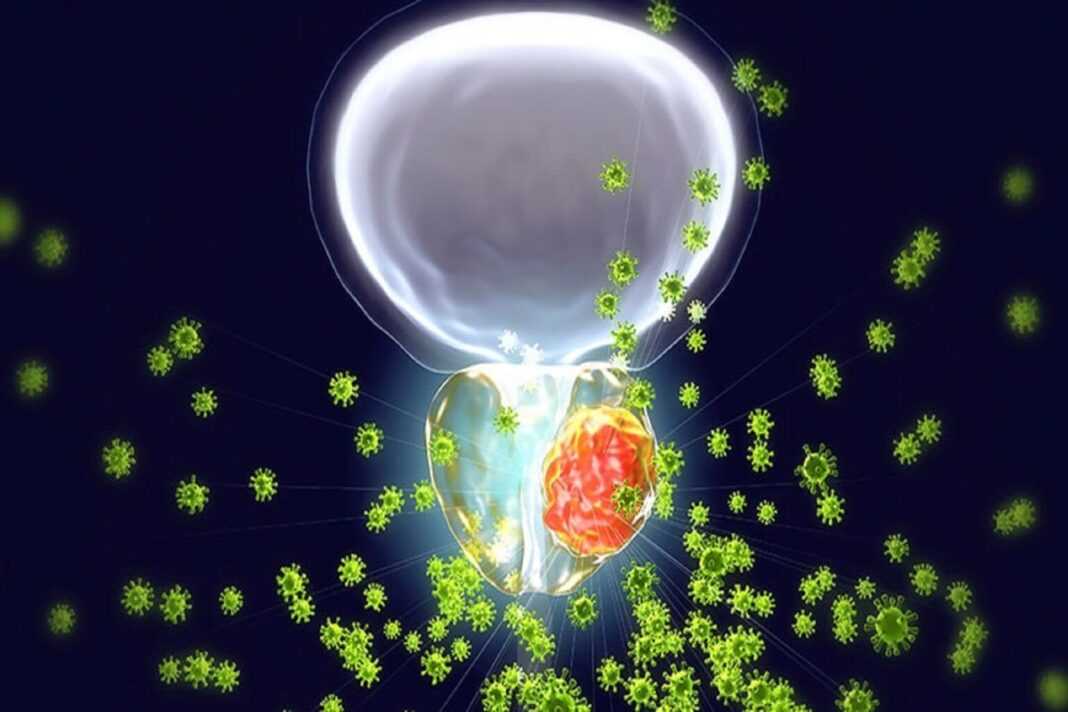

Έντερο Βακτήρια: Ένας βασικός πυλώνας θεραπείας για τον καρκίνο του προστάτη είναι η στέρησή του από ανδρογόνα, τις ορμόνες που τον κάνουν να μεγαλώνει. Οι όρχεις είναι η κύρια πηγή αυτών των ορμονών, επομένως η θεραπεία μπορεί να συνίσταται είτε στη χειρουργική αφαίρεση αυτών των οργάνων είτε στη χρήση φαρμάκων για τον αποκλεισμό της παραγωγής ορμονών τους. Με την πάροδο του χρόνου, ορισμένοι καρκίνοι του προστάτη γίνονται ανθεκτικοί σε αυτές τις θεραπείες και αρχίζουν να επεκτείνονται ξανά. Όπως συμβαίνει με πολλούς καρκίνους που εμφανίζουν αυτές τις συμπεριφορές, η εύρεση ακριβώς αυτού που τους κάνει ανθεκτικούς μπορεί να είναι δύσκολη.

Ένας ένοχος μπορεί να είναι βακτήρια που ζουν στο έντερο. Οι ερευνητές διαπίστωσαν ότι σε ευνουχισμένα ποντίκια και σε άτομα που λαμβάνουν θεραπεία στέρησης ανδρογόνων, ορισμένα από αυτά τα βακτήρια του εντέρου αρχίζουν να παράγουν ανδρογόνα που λαμβάνονται εύκολα στην κυκλοφορία του αίματος. Σύμφωνα με αυτά τα νέα ευρήματα, που δημοσιεύθηκαν στο περιοδικό Sciencce, τα ανδρογόνα φαίνεται να υποστηρίζουν την ανάπτυξη του καρκίνου του προστάτη και την αντοχή του στη θεραπεία.

Αυτή η μελέτη είναι η πρώτη που δείχνει ότι τα βακτήρια μπορούν να παράγουν τεστοστερόνη, αν και οι ερευνητές δεν είναι ακόμη σίγουροι τι τα ωθεί να ξεκινήσουν να το κάνουν αυτό. Η θεραπεία στέρησης ανδρογόνων μπορεί επίσης να οδηγήσει σε περισσότερα από αυτά τα μικρόβια που παράγουν ορμόνες στο έντερο, σύμφωνα με τα αποτελέσματα.